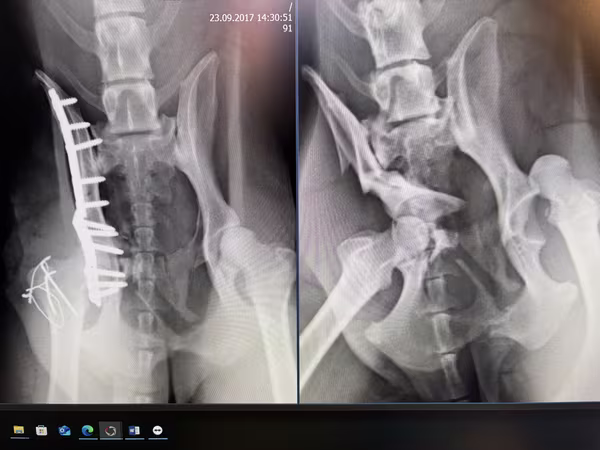

Ist der Stütz- und Bewegungsapparat bei Haustieren beeinträchtigt, kann dies zu einer Verminderung der Lebensqualität führen. Orthopädische Probleme, wie z.B. Knochenbrüche, Bänderrisse, Wachstumsstörungen, aber auch Schmerzen aufgrund von degenerativen Prozessen im Alter können unseren Patienten erhebliche Probleme bereiten. Zur Diagnosestellung ist die spezielle klinische Untersuchung durch einen erfahrenen Orthopäden der wichtigste Teil. Weiterhin können neben Laboruntersuchungen bildgebende Verfahren, wie Röntgen, CT oder Ultraschall, unterstützend herangezogen werden. Die Therapie kann nach Diagnosestellung von der konservativen Behandlung bis hin zur Operation reichen, um auf lange Sicht ein möglichst schmerzfreies und tiergerechtes Leben zu ermöglichen.